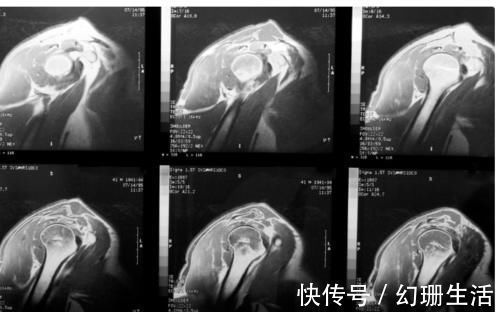

肩痛的治疗在大多数情况下可以由门诊医生成功地进行,并转诊给物理康复治疗师帮助改善患者的力学和力量也很重要。在诊断肩痛的过程中肩关节的X线和核磁共振检查至关重要,很容易判断肩痛引起的原因。